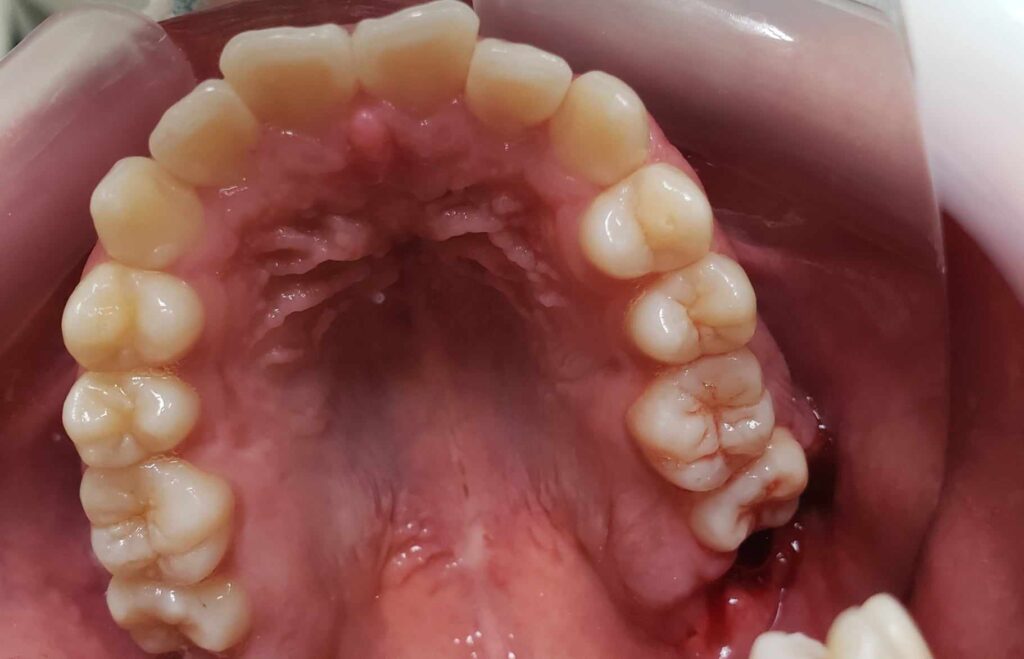

治療前

• 初診:2012年、9歳女児、

• 主訴:出っ歯と歯のがたがたが気になる。

• 診断:1級過蓋咬合、上下前歯叢生、上顎左右側切歯クロスバイト